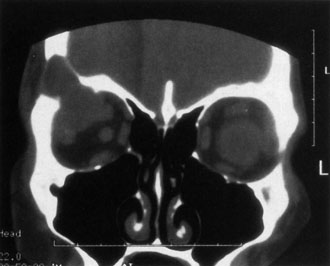

Investigations

If NFM is suspected, MRI should be ordered of the orbits and brain to exclude noncontiguous intracranial anomalies.93 Magnetic resonance imaging demonstrates the dilated cystic spaces with either a hypointense (lymphatic cyst) or hyperintense (hemorrhagic cyst) signal on T1-weighted images, and a hyperintense signal on T2-weighted images (Fig. 10, A&B).94Layering may be seen within the cysts if there has been a recent hemorrhage leaving unresorbed blood. The CT scans of patients with a deep NFM show low-density, poorly defined masses behind the orbital septum in the extraconal and intraconal spaces, which may indent the globe.3 Calcification within the mass (Fig. 11) and inhomogeneous enhancement of the rim and focal areas within the lesion may be seen that corresponds to abnormal endothelially lined channels.3 Enlargement of the bony orbit can occur, particularly with combined lesions.3,89 If the diagnosis is still unclear, ultrasonography can be performed. A cystic orbital mass is seen on B-scan. A-scan shows features of a solid, cellular tumor: low reflectivity, regular homogeneous internal structure, and marked sound attenuation through the mass.3,89 Standard pulsed Doppler ultrasound confirms no intrinsic flow within the lesions.

Fig. 11. Axial computed tomography scan of patient in Figure 9, showing poorly defined orbital mass with calcifications. (Courtesy of Nancy A. Tucker MD, Illinois Oculoplastic Associates)